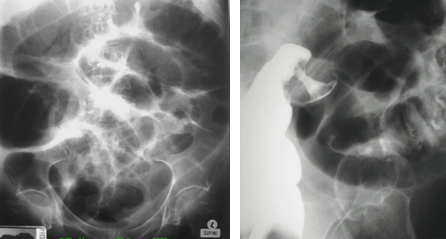

33yo patient presents with diarrhoea associated with crampy abdominal pain localised to the RLQ. Associated with this is a fever and mild arthralgia

Crohn’s disease

45yo male presents with two months of faecal frequency with loose stools, urgency and tenesmus. Associated with this is abdominal pain prior to defaecating and rectal bleeding

Ulcerative colitis